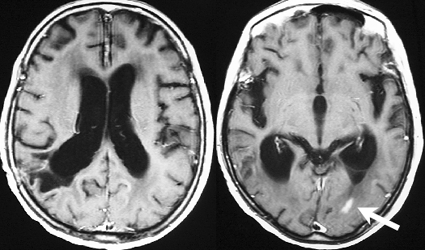

これは1990年代の古い例ですがリンパ腫の増大が早いことをお見せします。左側のはTHP-COPという化学療法をする前のものです。真ん中のは化学療法から4日目で,腫瘍は小さくなりました。でも,2コース目の化学療法の直前(4週間後)にもう一度MRIをしてみたらすごく大きくなっていました。この化学療法は効いているのだか効いていないのだか判らないことになります。化学療法を行なうならとても強い薬剤を使わなければなりませんし急がなければなりません。

矢印の所を定位脳手術で取りました。病理の結果がリンパ腫と確定されましたから,MTX化学療法をしてから放射線をあてたら,右側のMRIのように腫瘍は消えました。患者さんの症状は良くなって退院したのですがーー。

左から,1回目の再発,2回目の再発,3回目の再発です。再発するたびになんとか治療はできるのですが,違った場所に再発してきてだんだん治療が効かなくなってくることが多いです。このような現象から,脳のリンパ腫は脳に発生するのではなくて,体のどこかに原発巣があるのではないかという考えもあります。もちろん、こんな再発をしないで治ってしまう患者さんも多いです。